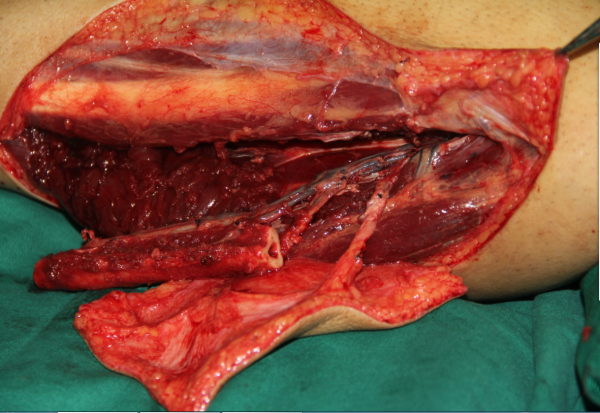

玉米机伤右足复合组织缺损,腓骨皮瓣修复,术后12天,伤口愈合良好,今日出院清创后

术中

跖趾关节成形